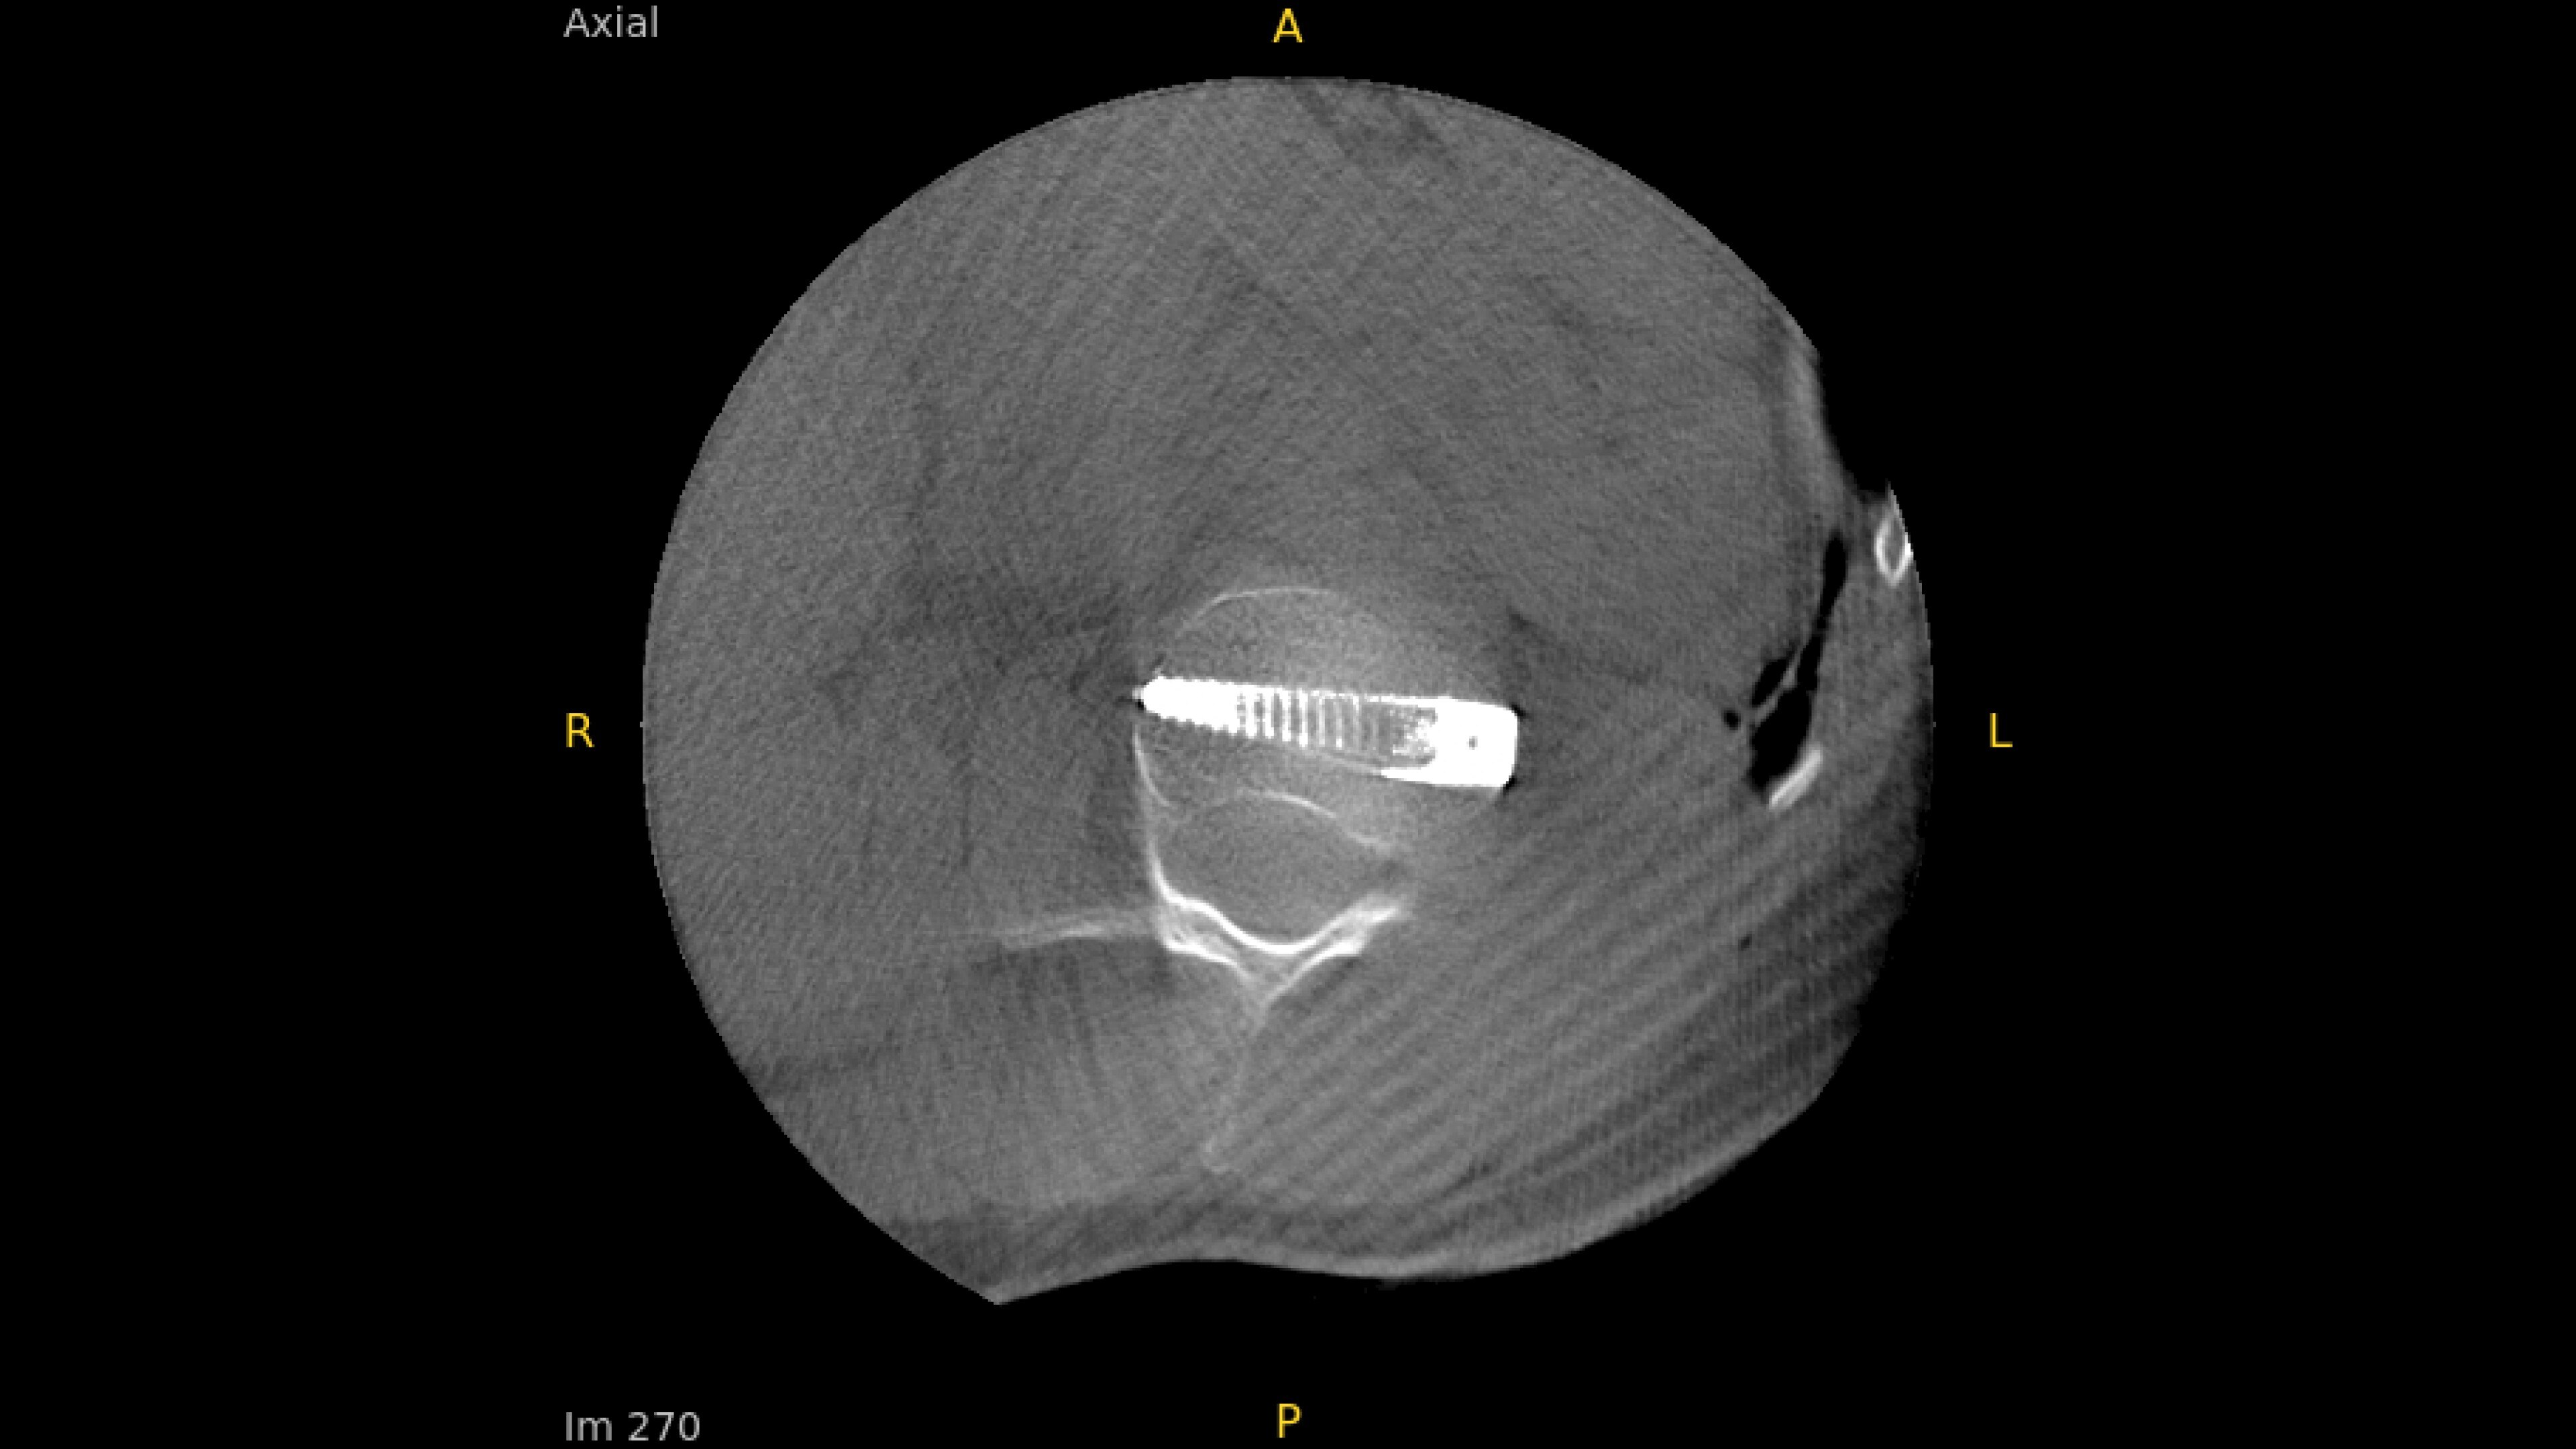

With OEC 3D, comprehensive imaging coverage of 19 cm x 19 cm x 19 cm 3D volumes and exceptional 2D images enables viewing several levels of the spine in the operating room.

The OEC 3D presents five perspectives: Axial, Coronal, Sagittal, MIP, and VR, on a 4K display for clear and detailed review of 3D volumes and 2D images

Analyze CT-like images with the OEC 3D Volume Viewer which includes Multi-Oblique, Area Measure, Window Level/Window Width, rotate, zoom, and more for quick and comprehensive visualization.